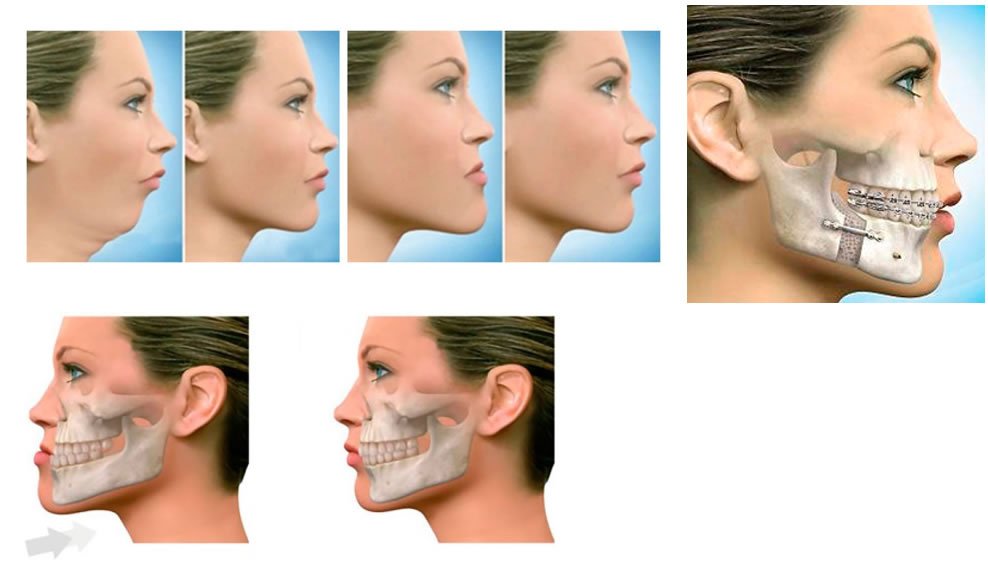

Cirurgia ortognática faz correção de mordida e melhora estética da face

A definição de cirurgia ortognática vem do latim “orto”, que significa correto, e “gnatos”, que vem de maxilares. Ou seja, significa colocar os maxilares na sua melhor relação, para promover estética facial e uma melhor oclusão (mordida). Estima-se que 25 a 30% da população apresenta algum grau de desamonia facial e que pelo menos a metade desse […]